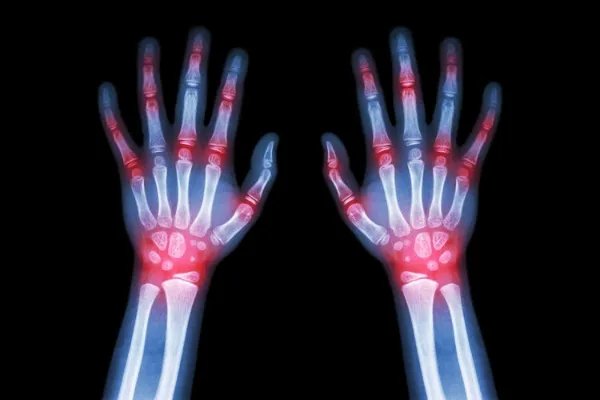

1、此类疾病是指母婴血型不合,母亲血液中对胎儿红细胞的产生免疫抗体,通过胎盘进入了胎儿的循环,发生免疫反应,导致胎儿新生儿,红细胞破坏而引起的溶血。

2、新生儿溶血病以a、b、o血型系统不合最为常见,其次是RH血型系统不合。

发生a、b、o血型不合溶血病的母亲多为o型血型,婴儿多为a型或b型。如母为ab型或婴儿为o型血型则均不会发生溶血。

3、HR血型不合溶血病主要发生在RH阴性孕妇和RH阳性胎儿当中,发生此类症状的病情严重程度和母亲产生的体型抗体量有直接的关系,抗体与婴儿红细胞结合程度及胎儿代偿能力有一定的关系。